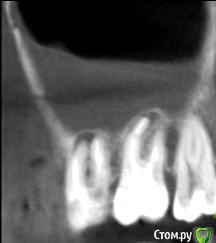

Helen22 Опубликовано 12 декабря, 2015 Автор Поделиться Опубликовано 12 декабря, 2015 Спасибо за оперативные ответы) промучилась с этим КТ(оно действительно для ЛОРа), но не смогла ничего в нем сделать.Сделала сегодня КТ 16, 17, 18 вот принт- скрины, правда не знаю насколько они будут информативными.... Ссылка на комментарий